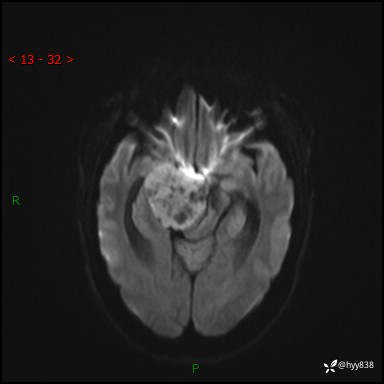

颅脑MRI平扫+增强